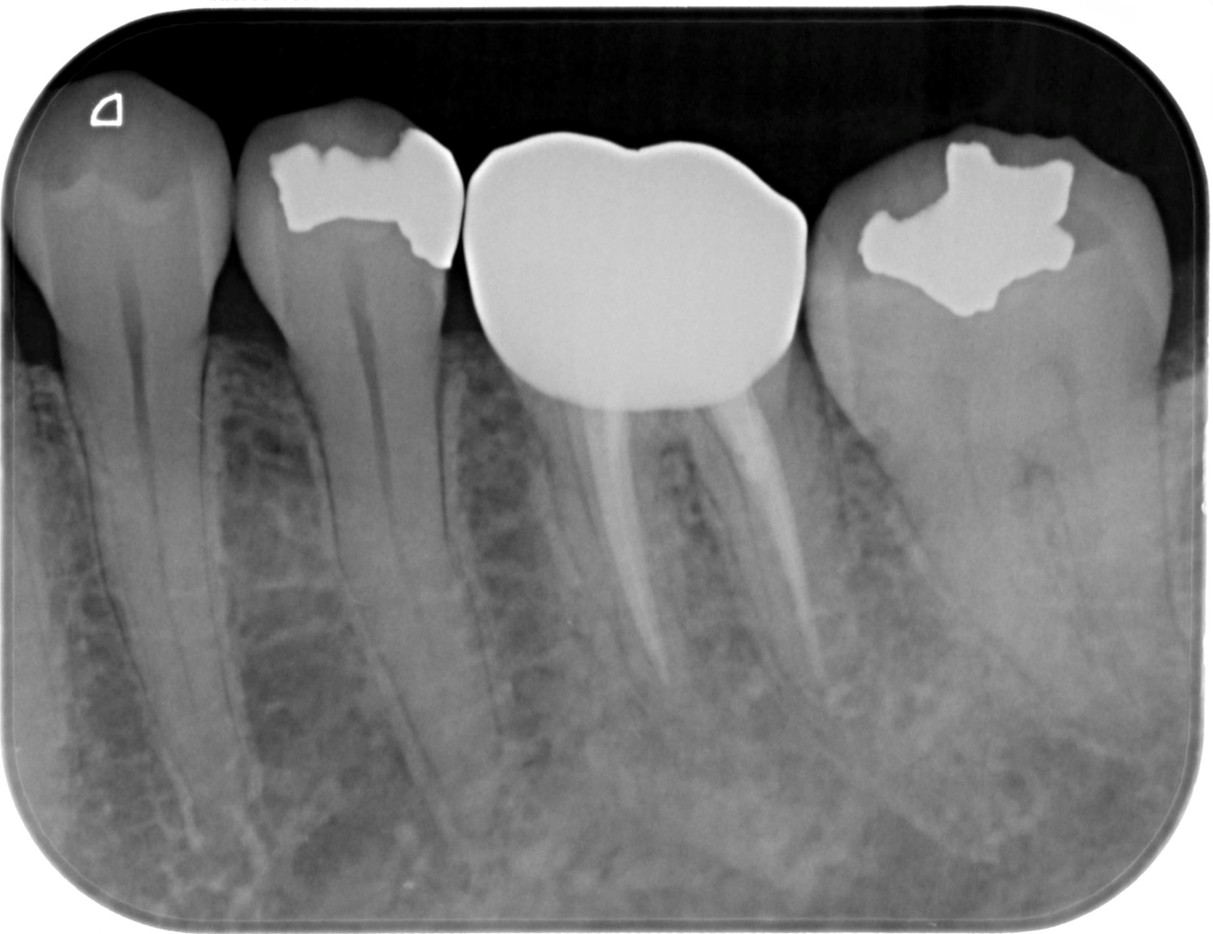

症例4

治療経過

①![]() 術前 |

②![]() 根管治療後3か月経過 |

③![]() 根管治療後1年経過時 |

④![]() 根管治療後2年経過時 |

神経の治療後、①→②→③→④と時間をかけて徐々に治ってくることがあります。

神経の治療は細菌感染を除去する治療です。細菌がいなくなれば、無駄に神経をとらなくても良い歯もあるかもしれません。

| 項目 | 詳細 |

|---|---|

| 患者様データ | 30代 男性 |

| 来院時の主訴 | 「他院で右上の歯3本とも神経をとる必要があると言われた。なんとか神経を残したい。」 |

| 術前検査結果 |

右上第一小臼歯:打診痛(+)・歯髄の生活反応有り 右上第二小臼歯:打診痛(+)・歯髄の生活反応無し 右上第二大臼歯:打診痛(ー)・歯髄の生活反応有り |

| 医院の診断 |

右上第一小臼歯:健全→術前に神経が残せる可能性のある歯と診断 右上第二小臼歯:慢性根尖性歯周炎→術前に神経が残せない歯と診断 右上第二大臼歯:無症候性可逆性歯髄炎→術前に神経が残せる可能性のある歯と診断し、術中に神経を残せると診断 |

| 通院期間 | 2年半 |

| 来院回数 | 10回(定期的なチェック含む) |

| 治療費 | 350,000円(税抜) 《内訳》 右上第二小臼歯:精密根管治療70,000円、ファイバーポストコア20,000円、セラミック治療120,000円 右上第二大臼歯:歯髄温存療法55,000円、セラミック治療85,000円 |

| リスクと副作用 | ①根管治療歯は長期的には破折するリスク ②メインテナンスが必要 |

| ココがこだわりのポイント☝ |

レントゲン検査や患者様の訴える症状だけでは神経を残せるかどうかは断定できません。 この方もレントゲン写真上では神経を残せないように見える歯でしたが、治療前に検査を入念に行うことで残せる可能性を見出すことができました。 同じ悩みを抱えた方は是非お気軽にご相談下さい。 |